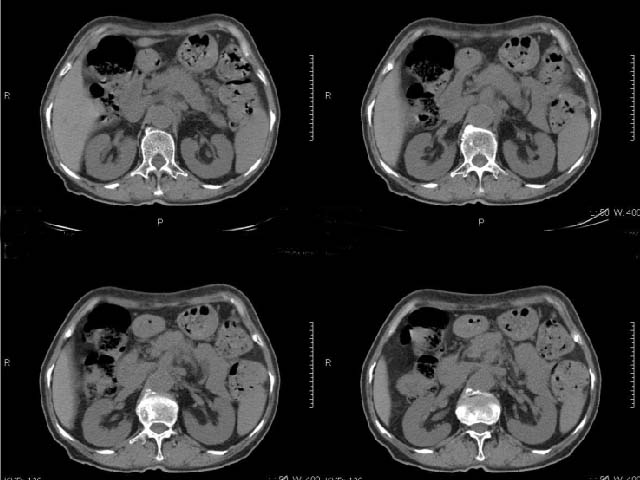

女,69岁,浑身乏力,腹泻半年余,无腹疼,排泄物中含有脂肪球,抗炎治疗一周仍不缓解,来我院检查发现明显低钾血症,给予补钾(氯化钾)一周后,血钾恢复正常,经化验检查,尿钾持续明显高于正常,临床考虑患者不仅消化道失钾,还伴有泌尿系统失钾,故进行ct增强检查看肾上腺是否有病变。ct表现为胰腺肥大,而且体尾部强化较弱,明显呈稍低密度,胰尾见有更低密度,而且胰腺与周围组织的脂肪间隙不清,大血管周围似乎有包绕现象,患者是否有过胰腺炎病史,家属说不清楚;而双侧肾上腺大小形态,本人认为未见异常,本人倾向于考虑:慢性胰腺炎伴假性囊肿,不排除胰腺占位可能;但是不知怎么解释持续尿钾现象。请大家发表高见!

静脉期